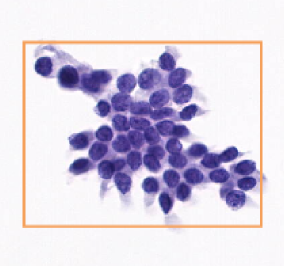

Block interception and precise amplification of gastric biopsy digital images; Tumor segmentation model

and heat map analysis; Feature extraction, negative and positive classification to predict tumor probability with high sensitivity.

1. Identification image: high-quality, direct, accurate, intelligent.

2. Thermal analysis: show the risk level in each area, locate abnormal follicular cells and make an intelligent rank for quick review,

visualize each phase and one-click for online report.

3. WSI reasoning: WSI slide-window reasoning, intelligent zoom in, adenoma identification optimization.